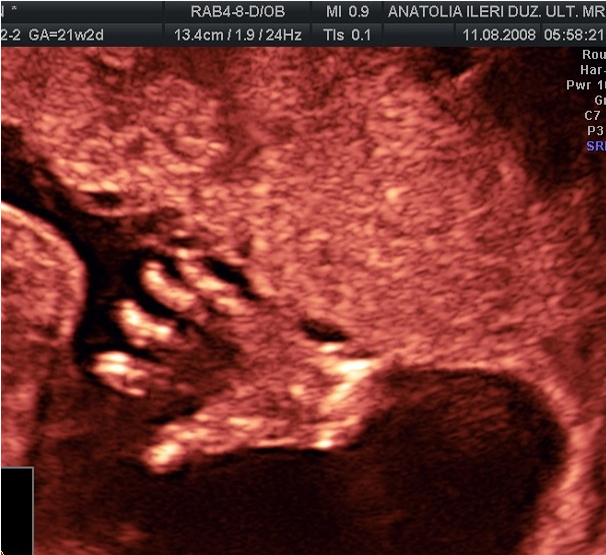

OMURGANIN YAN PLANDA İNCELENMESİ